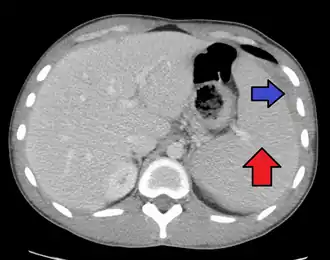

Splenomegaly due to mononucleosis resulting in a subcapsular hematoma

Spleen enlargement is common in the second and third weeks, although this may not be apparent on physical examination. Rarely, the spleen may rupture.[27] There may also be some enlargement of the liver.[25] Jaundice occurs only occasionally.[16][28]

Splenomegaly is a common symptom of infectious mononucleosis, and healthcare providers may consider using abdominal ultrasonography to get insight into the enlargement of a person's spleen.[61] However, because spleen size varies greatly, ultrasonography is not a valid technique for assessing spleen enlargement. It should not be used in typical circumstances or to make routine decisions about fitness for playing sports.[61]